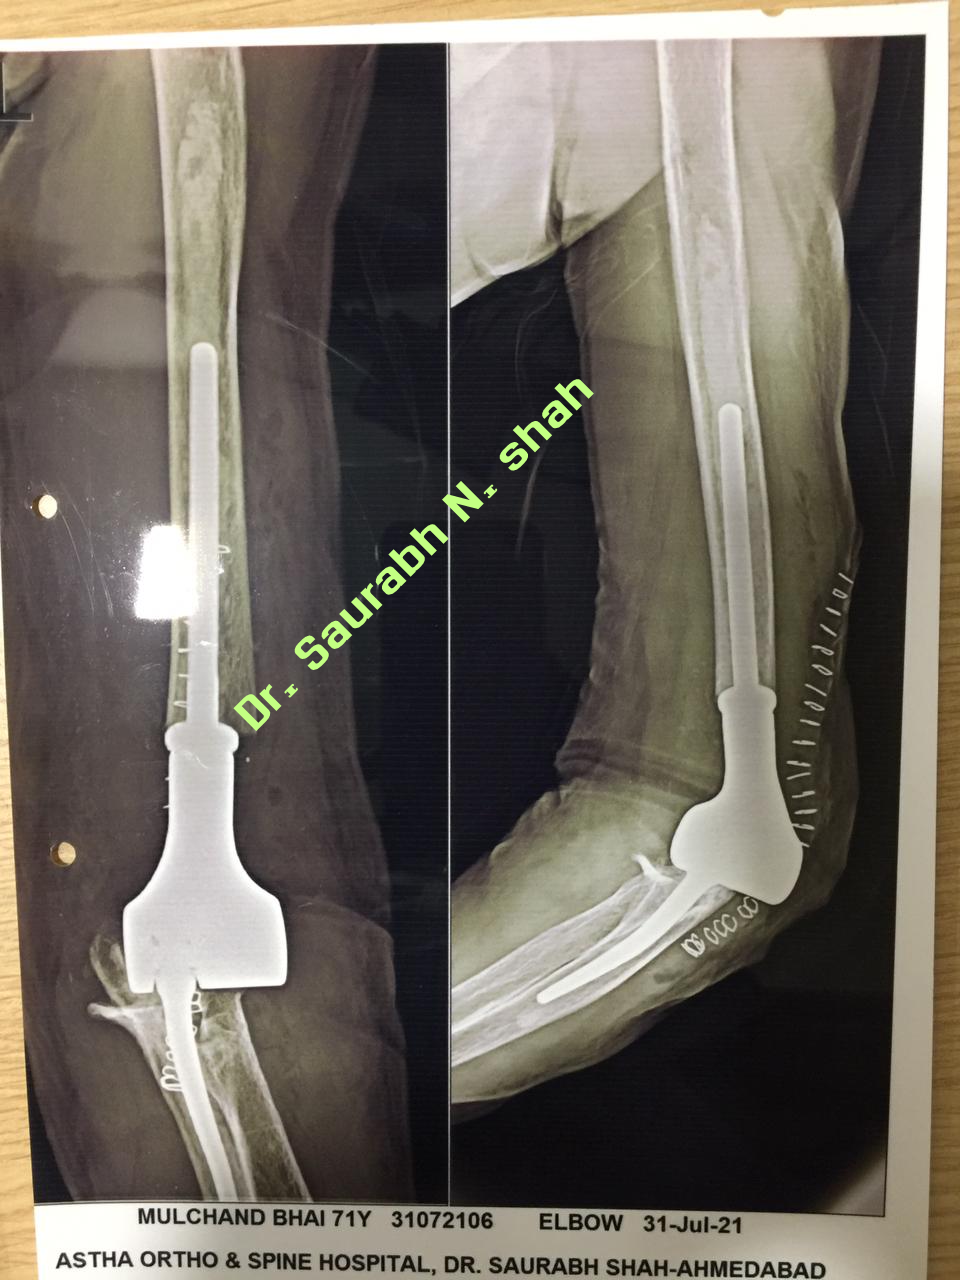

Elbow Joint Replacement